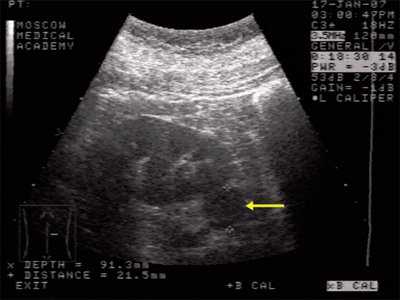

При классической картине АМЛ в почке определяется гиперэхогенное (по отношению к паренхиме почки) образование с четкими контурами, не дающее акустической тени, округлой формы, акустическая плотность которого соответствует плотности жировой ткани, структура опухоли однородная во всех отделах (рис. 2, 3).

В паренхиме почки визуализируется гиперэхогенное образование с четкими контурами, небольшого размера, без акустической тени.